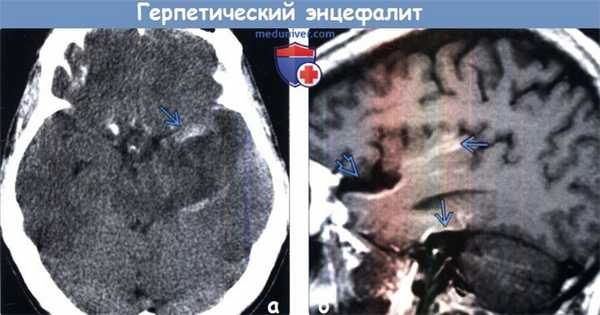

(а) Бесконтрастная КТ, аксиальный срез: у новорожденного с ВПГ-2-энцефалитом определяются протяженные зоны снижения плотности серого и белого вещества. У 27% инфицированных новорожденных признаков заболевания при первичной бесконтрастной КТ не наблюдается.

(б) МРТ, ДВИ, аксиальный срез: у двухнедельного ребенка с судорожным синдромом и выбуханием родничка визуализируется распространенное ограничение диффузии в области структур серого и белого вещества без четкой локализации ЕЯ. Были выявлены увеличение IgM и положительный результат ПЦР против ВПГ. ДВИ имеет большое значение в ранней диагностике этого состояния. (а) МРТ, Т2-ВИ, корональный срез: у младенца, у которого в перинатальном периоде был диагностирован ВПГ-2-энцефалит, определяются распространенная кистозная э нцефаломаля-ция с выраженным расширением боковых желудочков заместительного генеза.

(б) Патологоанатомический макропрепарат головного мозга новорожденного, корональный срез: определяются изменения, вызванные вертикально переданной ВПГ-2-инфекцией, включающие расширение желудочковой системы, кистозную энцефаломаляцию и отсутствие нормального рисунка извилин коры. Внутриутробную передачу имеют около 5% всех ВПГ-2-инфекций у новорожденных.